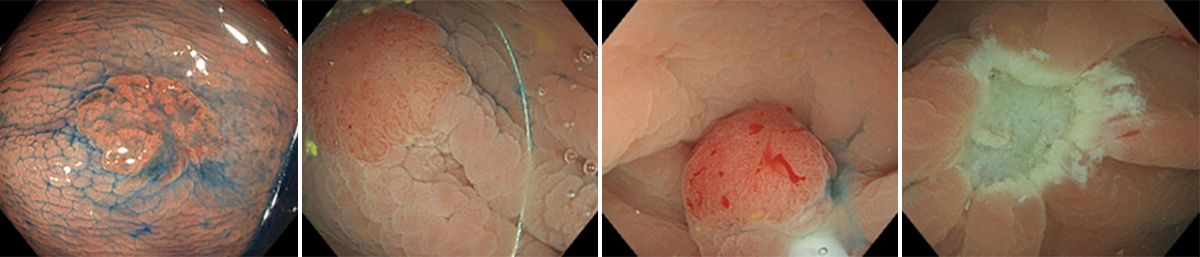

一方で、腫瘍が大きい場合でEMRやUnderwater EMRでは一括切除が難しい場合には、大腸粘膜下層剥離術(ESD)を行います。ESDでは専用の器具を用いて病変の周囲を切開し粘膜下層を剥離しながら切除することで、大きな腫瘍であっても一括切除が可能です(図4)。

切除した組織は回収し、病理検査を行います。病理検査では、腫瘍の深さや切除断端の状態、脈管侵襲の有無などを確認し、治療が内視鏡で完結できているかを評価します。さらに当科では病理診断科と連携し、切除標本について病理カンファレンスで丁寧に検討しています。